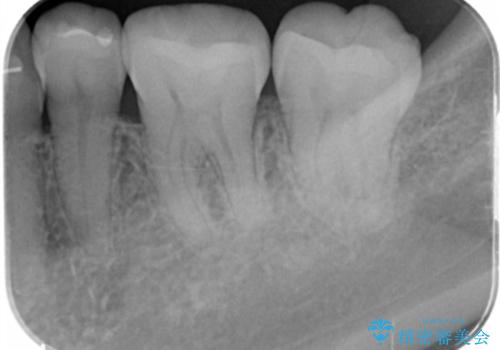

e-maxインレー治療

- 過去に治療した銀の詰め物が取れて来院された患者様です。

詰め物のやりかえをするのなら白い詰め物でやりかえたいとのことなのでe-maxインレーでの治療を行いました。